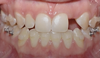

Figure 14 through Figure 18 show a partially dentate patient for whom a fully digital workflow was utilized. This 47-year-old male presented with root blunting and mobility of teeth Nos. 7, 8, and 9 (Figure 14). A thermoplastic clip was attached during the CBCT, and an intraoral scan was taken and superimposed on the CBCT. The case was then planned in the navigation planning software (Figure 15). Once the teeth were extracted, intraoral scanning was performed. The intraoral scan was imported into lab software (Figure 16), and a PMMA milled screw-retained prosthesis was fabricated. The prosthesis was placed the next morning (Figure 17). Two months later, a new intraoral scan was taken to capture the mature soft tissue, and the final milled titanium abutment and restoration were delivered (Figure 18).

Fig 14. Preoperative view of a partially dentate case. Patient with root blunting and grade 3 mobility.

Figure 14

Fig 17. Views of the milled PMMA screw-retained provisional restoration. Note the screw access holes in the incisor edges (left panel). (Images courtesy of Dr. Kim Knoll.)

Figure 17

Fig 18. Placement of the final prosthesis. Milled titanium abutments (left panel) and Emax crowns (right panel). (Images courtesy of Dr. Kim Knoll.)

Figure 18